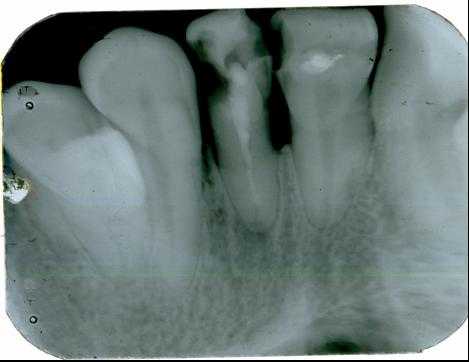

1. Внутриротовая контактная рентгенография

Основой рентгенологического исследования при большинстве заболеваний зубов и пародонта по-прежнему служит внутриротовая рентгенография.

На одном снимке можно получить изображение не более 2-3 зубов